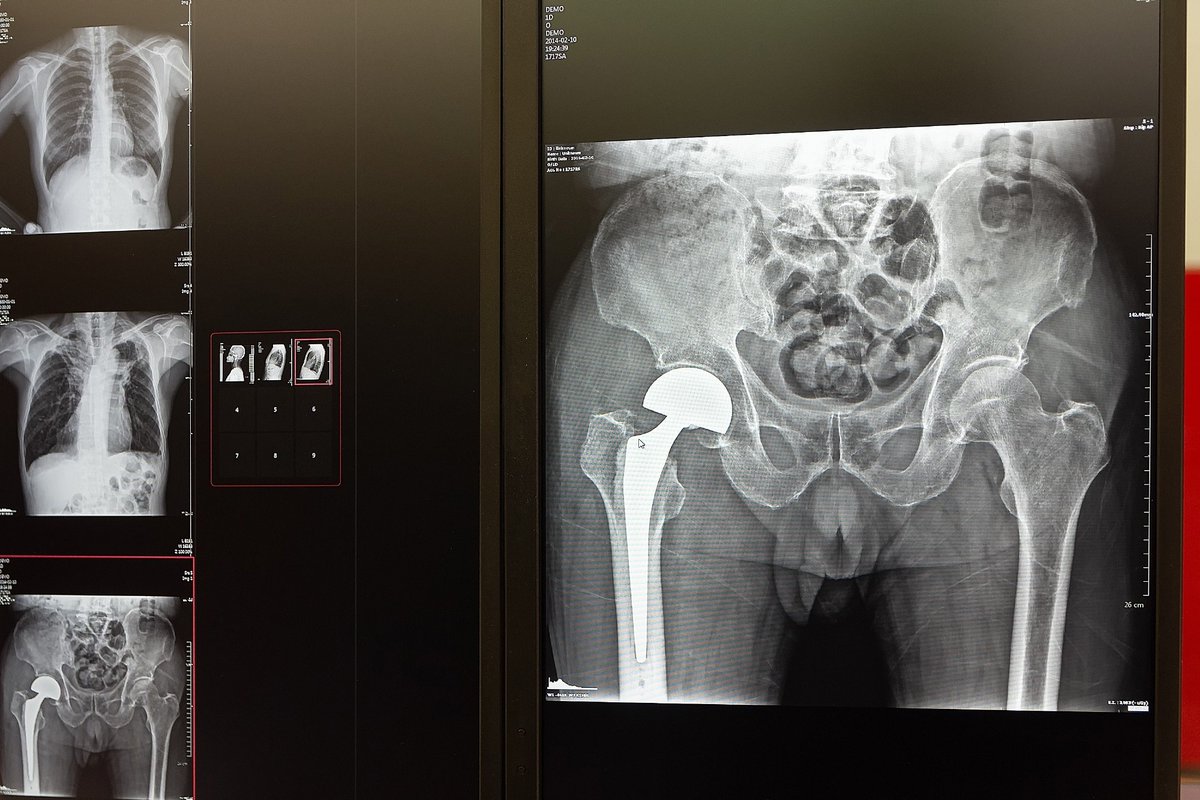

Hip replacement This is how both hip replacements look on an x-ray Statistically, a fracture occurs in 90% of cases at the age of 60+ and in women. The reason here is osteoporosis (leaching of calcium from bones) during menopause . . . . #HipReplacement #Orthopedics #Xray

Smart1Doctor1's tweet image. Hip replacement

This is how both hip replacements look on an x-ray

Statistically, a fracture occurs in 90% of cases at the age of 60+ and in women. The reason here is osteoporosis (leaching of calcium from bones) during menopause